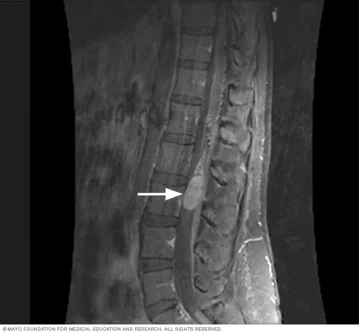

- Risonanza magnetica (RM): esame di riferimento per individuare la sede e l’estensione della lesione;

I tumori a origine nervosa coinvolgono le strutture che circondano o attraversano la colonna, come midollo spinale, radici nervose e meningi. Possono svilupparsi all’interno del canale vertebrale e vengono classificati in base alla loro posizione rispetto al midollo:

I tumori della colonna vertebrale rappresentano un gruppo di patologie complesse che possono coinvolgere le vertebre (tumori di origine ossea) oppure le strutture nervose come il midollo spinale, le radici nervose e le meningi (tumori di origine nervosa). Anche se si tratta di condizioni relativamente rare, la loro diagnosi precoce e il corretto inquadramento sono fondamentali per evitare danni neurologici e preservare la stabilità e la funzionalità della colonna.